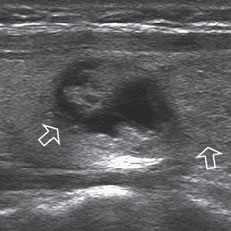

Un nódulo coloideo mixto puede aparecer como un quiste con un nódulo mural isoecogénico, excéntrico, que protruye hacia el lumen simulando una formación papilar, habitualmente vascularizado, que no corresponde a tejido neoplásico (Figura 19a). Si el componente sólido está rodeado por fluido, separado de la pared, y además tiene focos hiperecogénicos, es más difícil confundirlo con un tumor quístico (Figura 19b y c).

Figura 19. a) Nódulo coloideo, que muestra

una proyección de aspecto papilar hacia

el lumen, que corresponde a tejido no

neoplásico, igualmente vascularizado que

el resto del componente sólido del nódulo

(flecha abierta); b) y c) Nódulo coloideo,

predominantemente quístico, con componente

sólido (flecha), que muestra una forma

vegetante completamente rodeada de

coloide, con dos focos puntiformes en el

área más central.